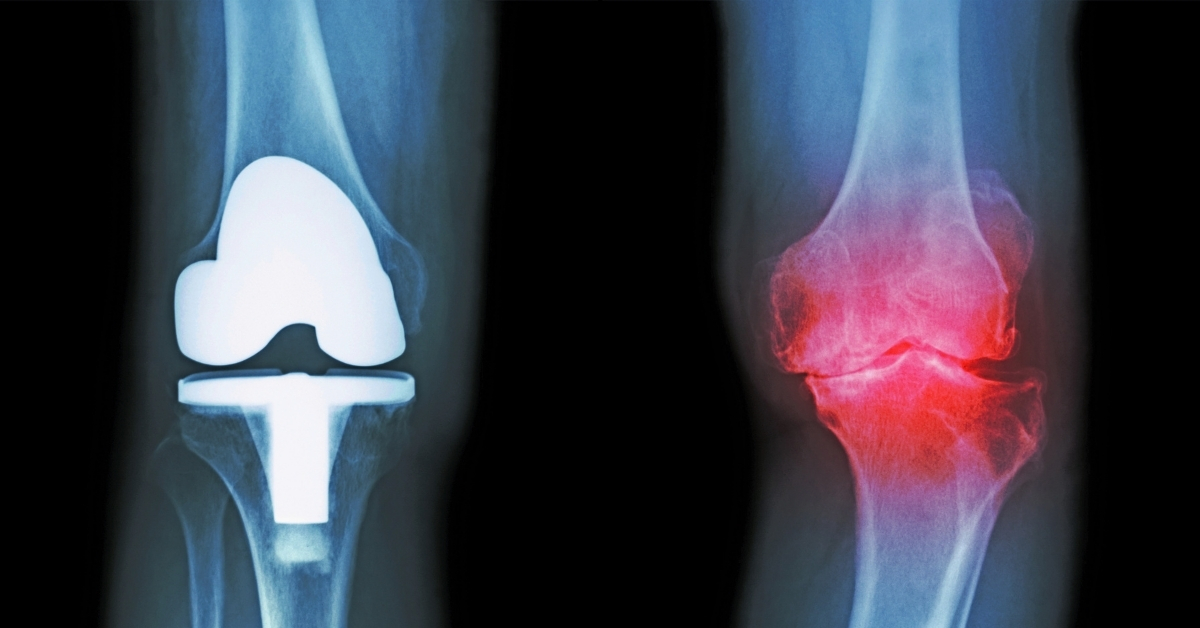

軟骨の摩耗が進んでしまうと、これを自然に戻す方法はないため、人工関節に入れ替える手術を行います。

今後、再生医療なども発展していくと思いますが、現状では人工関節置換術(手術)がスタンダードな治療法です。

膝関節の治療法として確立されている「人工関節置換術」は、厚生労働省のデータによると平均年齢は76歳と、比較的高齢の方が受けています。(※厚生労働省 第1-9 回NDB オープンデータ)

その一因としては、人工関節の耐久年数は20年ほどとされており、60代で手術した場合は80歳頃に、人工関節を入れ替える二度目の手術を行うことが想定されるからです。

※ レントゲン画像左側が右膝:人工関節、画像右側が変形が進行した変形性膝関節症(赤塗り)